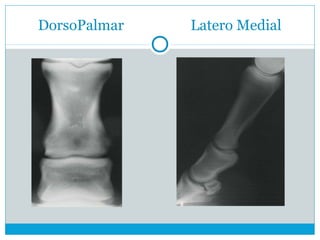

DorsoPalmar Latero Medial

 DorsoPalmar

 LM